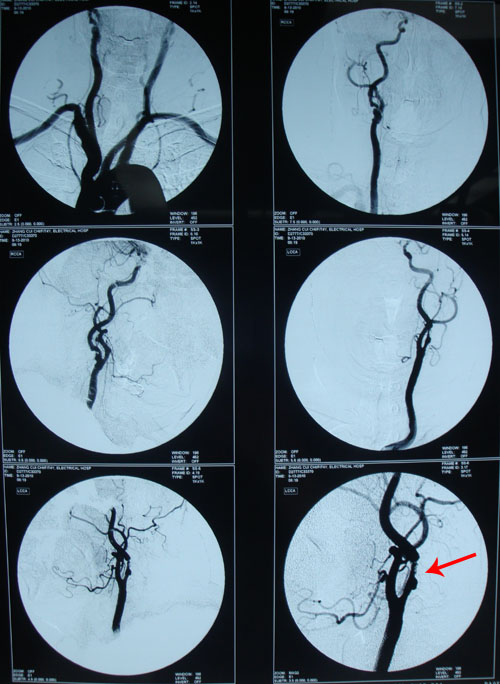

颈动脉造影:主动脉造影弓部各分支血管显影正常。双侧颈总动脉未见异常征象。双侧颈内动脉近端见管腔充盈缺损及重度狭窄,左侧狭窄约95%以上,右侧狭窄约75%,双颈内动脉末段血管见管壁轻度不光滑改变。双侧大脑前、大脑中动脉血管显影基本正常。右椎动脉显影纤细,左椎动脉开口及近段见血管轻度狭窄改变。基底动脉及小脑动脉血管显影尚好。

血管超声示:脑动脉硬化血流频谱改变,左侧颈内动脉虹吸段流速增快,左侧椎动脉血流速度增快;双侧颈动脉内膜增厚;多发斑块形成,左侧颈内动脉重度狭窄(70%-99%);双下肢股总动脉内膜增厚、多发斑块形成,双下肢静脉未见异常。